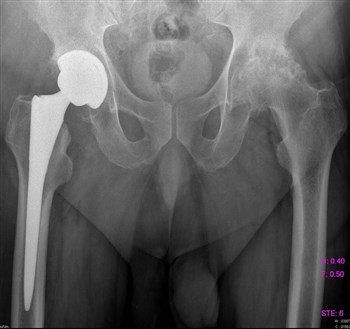

Артроз тазобедренного сустава

Все чаще и чаще пациенты обращаются с жалобами на боли в паху, в колене, иногда на боль в ноге, на скованность движений, нарушение походки.

Как правило, страдают таким недугом женщины после 40 лет.

Боль локализуется в вышеуказанных местах как на одной, так и на обеих ногах.

Для того, чтобы поставить верный диагноз, проводят диагностику, которая включает:

- МРТ;

- Рентгенографию;

- Компьютерную томографию.

Проведенная диагностика покажет, в какой стадии находится заболевание, будет дана точная информация о состоянии мягких и костных тканей.

Если заболевание не в хронической форме, или, проще говоря, не запущено, то лечение происходит обычным парацетамолом, без какого-либо хирургического вмешательства. Лечащий доктор назначает курс массажа, лечебной гимнастики, постоянный контроль ортопеда. При ноющих болях прописывается курс болеутоляющих – Кеторол, Диклофенак.

Немаловажное значение имеет обувь. Она должна быть качественной, лучше ортопедической.